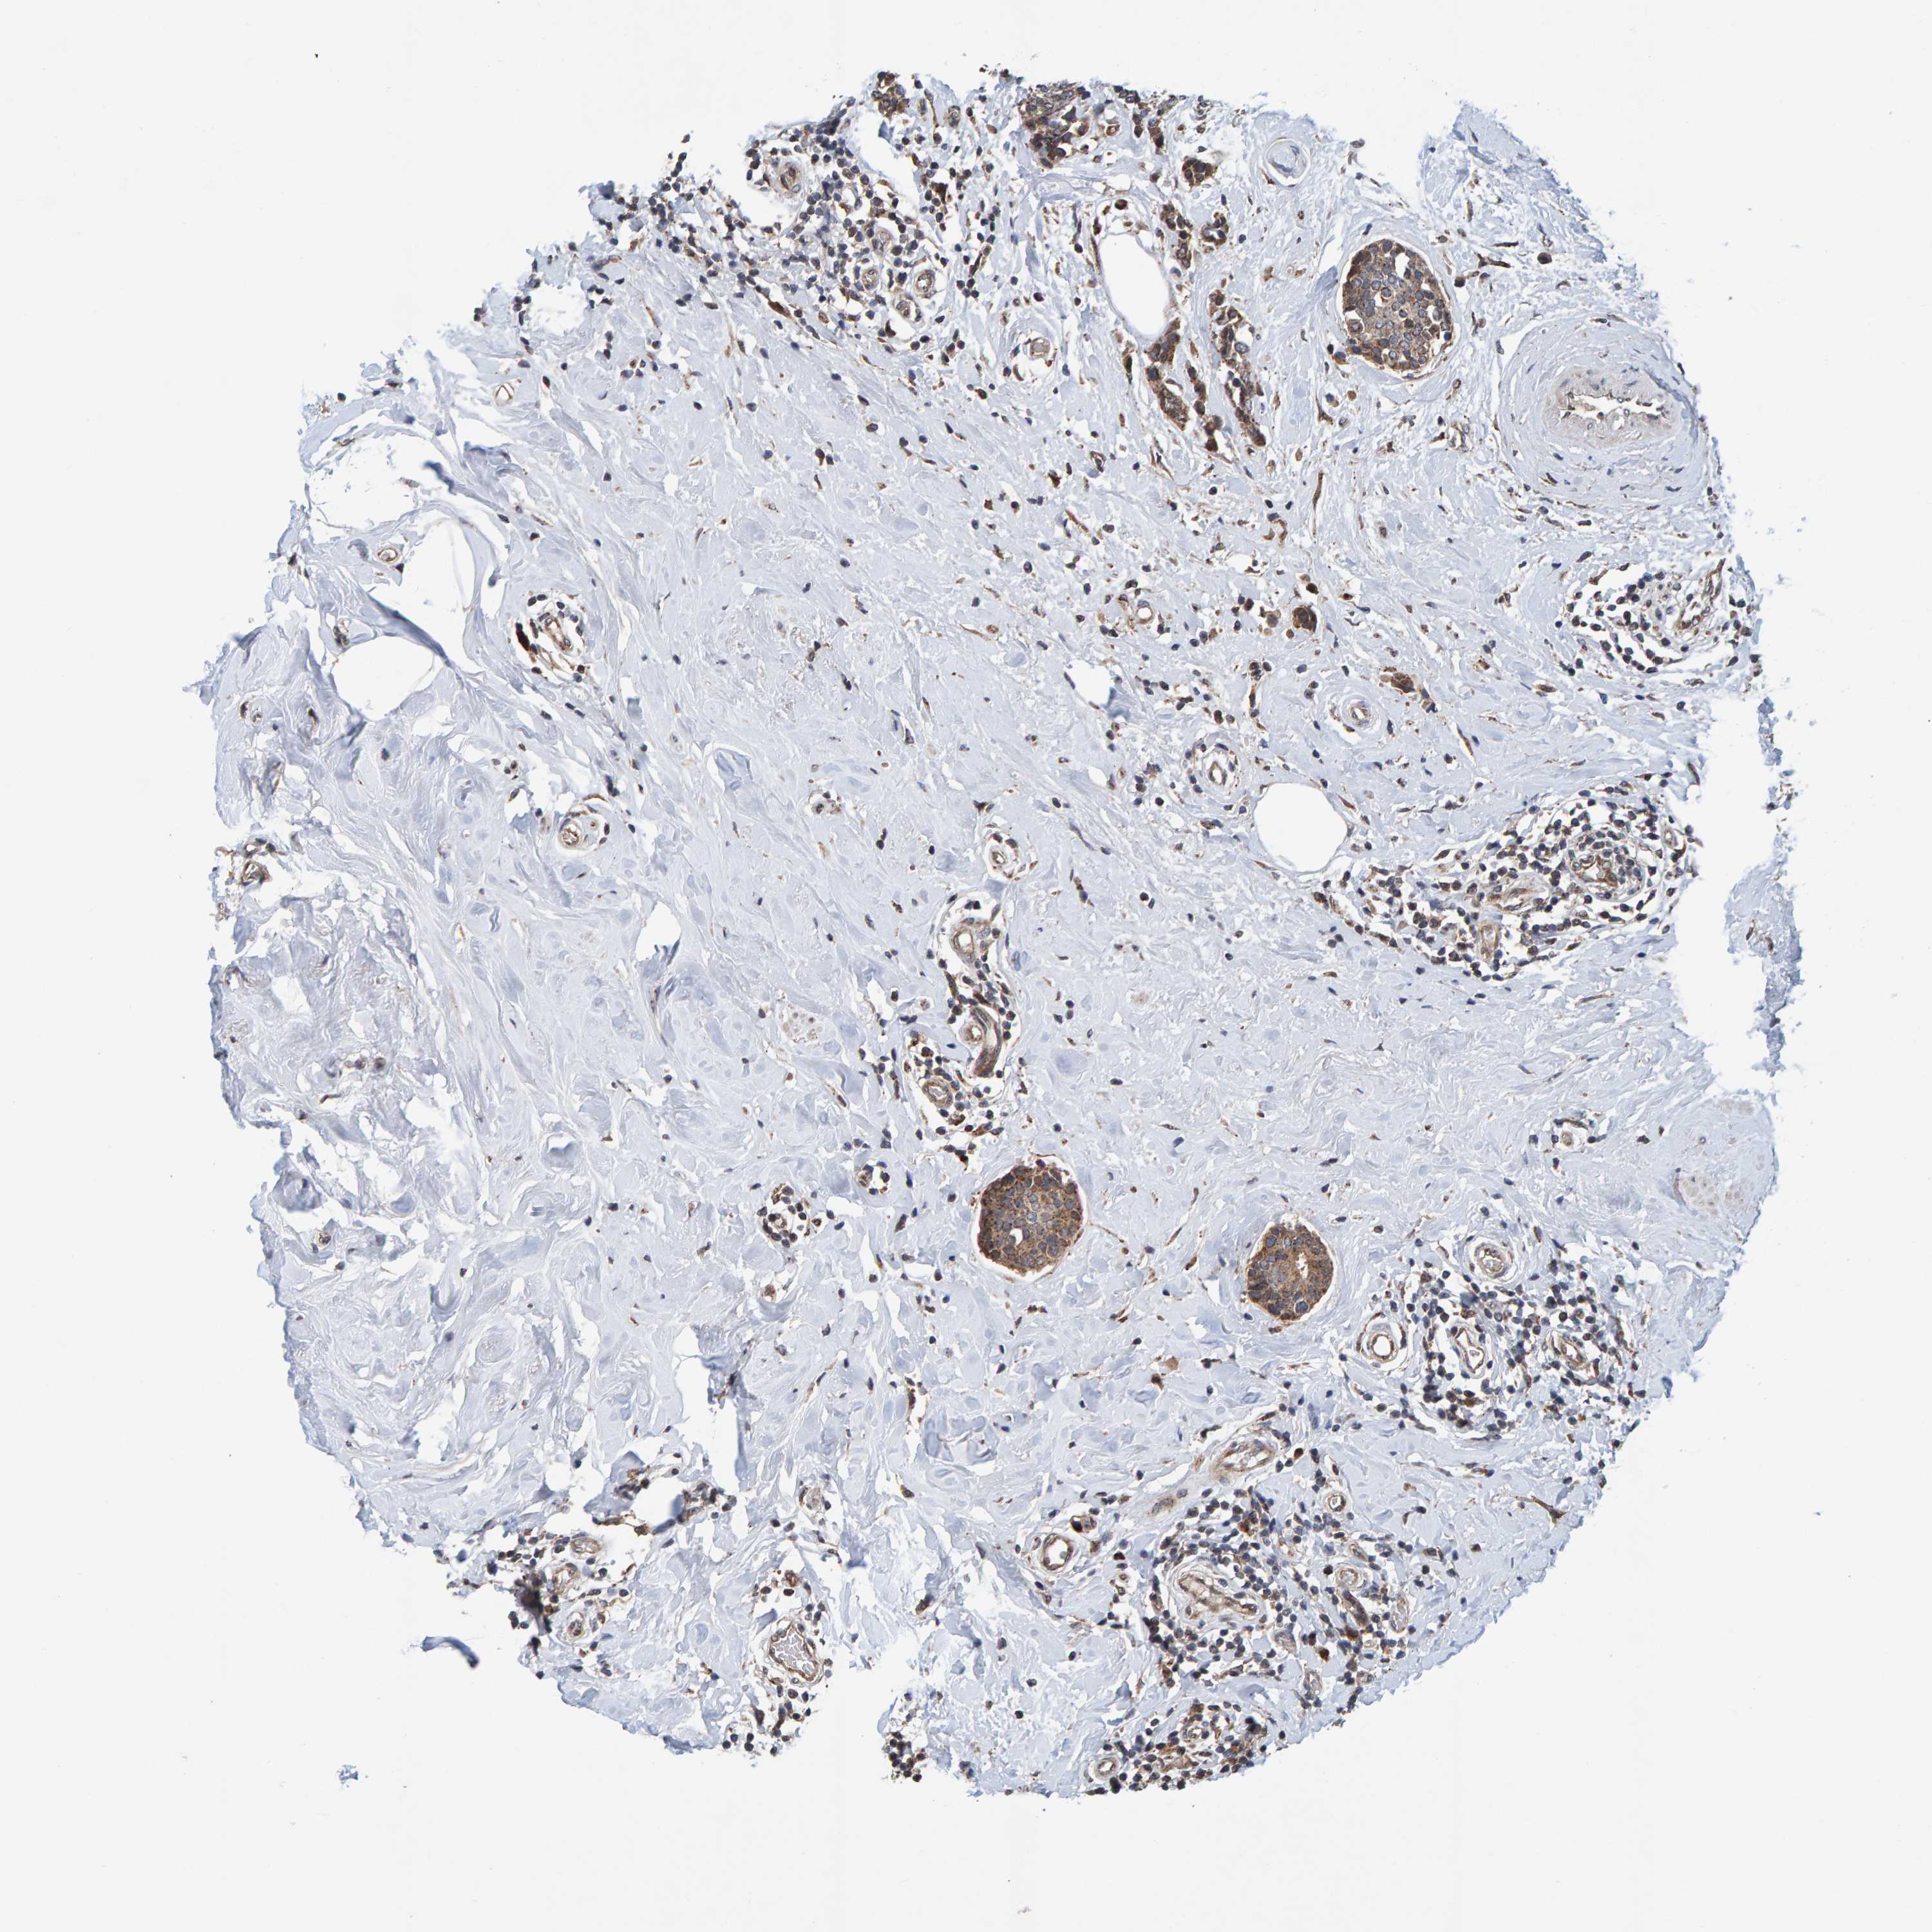

BRCA TCGA BRCA VALIDATION PROTEIN EXPRESSION

ANTIBODIES

AND

VALIDATION